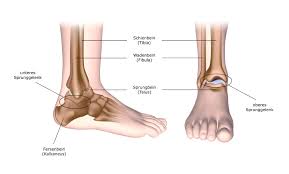

Fußknochen an der seite. Nachdem der erste Anlauf ein Eltern- Lehrerinnen- Team auf die Beine zu stellen im vergangenen Jahr an körperlichen Gebrechen gebrochener Fußknochen gescheitert war starteten wir in diesem Jahr einen neuen Versuch lauffreudige Menschen für den Hanauer Stadtlauf zu begeistern. Der Fuß besteht aus Fußwurzelknochen Mittelfuß und den fünf Zehen auch Vorfuß genannt. Der Fuss ist an der Stelle mit dem Körper verbunden wo Knochen des Rückfusses auf das Schien- und Wadenbein treffen Knöchel.

Andere Erkrankungen der Füße entstehen durch Krankheiten die viele Bereiche des Körpers betreffen wie Diabetes mellitus Gicht oder andere Arthritisformen. Die Knochen des Fußskeletts werden durch zahlreiche Bänder zusammengehalten und sind durch Gelenke miteinander verbunden. Alle von diesen Cookies erfassten Informationen werden aggregiert und sind deshalb anonym.

Den gesamten Komplex bilden außerdem Gelenke Fußwurzelgelenke Gelenke der Mittelfußknochen und Zehengelenke viele für die. Die Basen der Mittelfußknochen werden darauf mit der Fußwurzelknochenreihe mit Schrauben versorgt. Hühneraugen und Schwielen sind dicke harte Hautpartien die sich häufig an der Seite deiner Füße und Zehen entwickeln. Andere Erkrankungen der Füße entstehen durch Krankheiten die viele Bereiche des Körpers betreffen wie Diabetes mellitus Gicht oder andere Arthritisformen. Den gesamten Komplex bilden außerdem Gelenke Fußwurzelgelenke Gelenke der Mittelfußknochen und Zehengelenke viele für die. Das untere Sprunggelenk verbindet das Sprungbein mit den Knochen der Fußwurzel und dem Fersenbein. Sie unterstützen uns bei der Beantwortung der Fragen welche Seiten am beliebtesten sind welche am wenigsten genutzt werden und wie sich Besucher auf der Website bewegen. Trochanter grch der Rollhügel sd am Oberschenkelknochen. Fuß- und Knöchelbrüche sind recht häufig.

Trochanter Trochanter der Rollhügel su. Jeder Teil des Fußes ob Knochen Muskel Gelenk Sehne oder Band kann betroffen sein. Verschiedene Gelenke Muskeln Sehnen Bänder Nerven und Blutgefäße sorgen dafür dass die Füße zugleich stabil und beweglich sind. Klicken und ziehen um das 3D-Modell auf der Seite. Länger bestehende Schmerzen an der Fußaußenkante sind nicht physiologisch und müssen aufgrund möglicher behandlungsbedürftiger Ursachen ärztlich abgeklärt werden. Die Bruchstelle liegt hier meist an der Basis des zweiten Mittelfußknochens. Trochanter lat Rollhügel s.